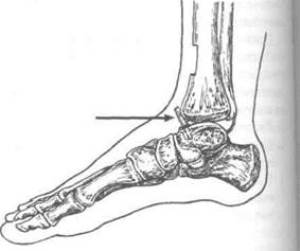

Задний предназначен для того, чтобы предупредить окончательное отвисание (чрезмерное сгибание) стопы, даже если произошел паралич всех мышц в этой части тела. При этом трансплантант вводится в пяточную кость таким образом, чтобы он упирался верхушкой в большеберцовую кость. Разработано несколько методик проведения этой операции.

Передний артрориз проводят как при параличе, так и если его нет. Во время этой операции трансплантант вводят в область таранной кости так, чтобы при разгибании стопы ее шейка упиралась в большеберцовую кость. Иногда проводят двойной артрориз, при котором объединяют техники заднего и переднего артрориза. Один из видов такой операции называют операцией Бойчева.